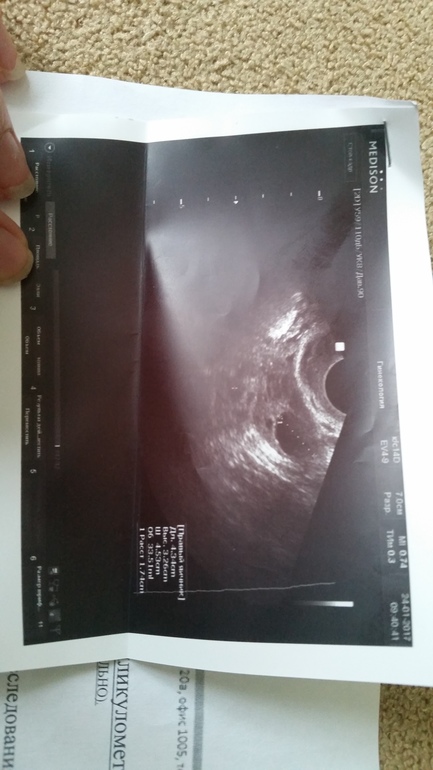

Была на фоликулометрии...

Но.. так увеличены яичники...и четко видно что есть утолщение...

У меня анализы все хорошие !

Но по узи овуляции нет и фоликул с прошлого месяца остался. Взяли мазки.